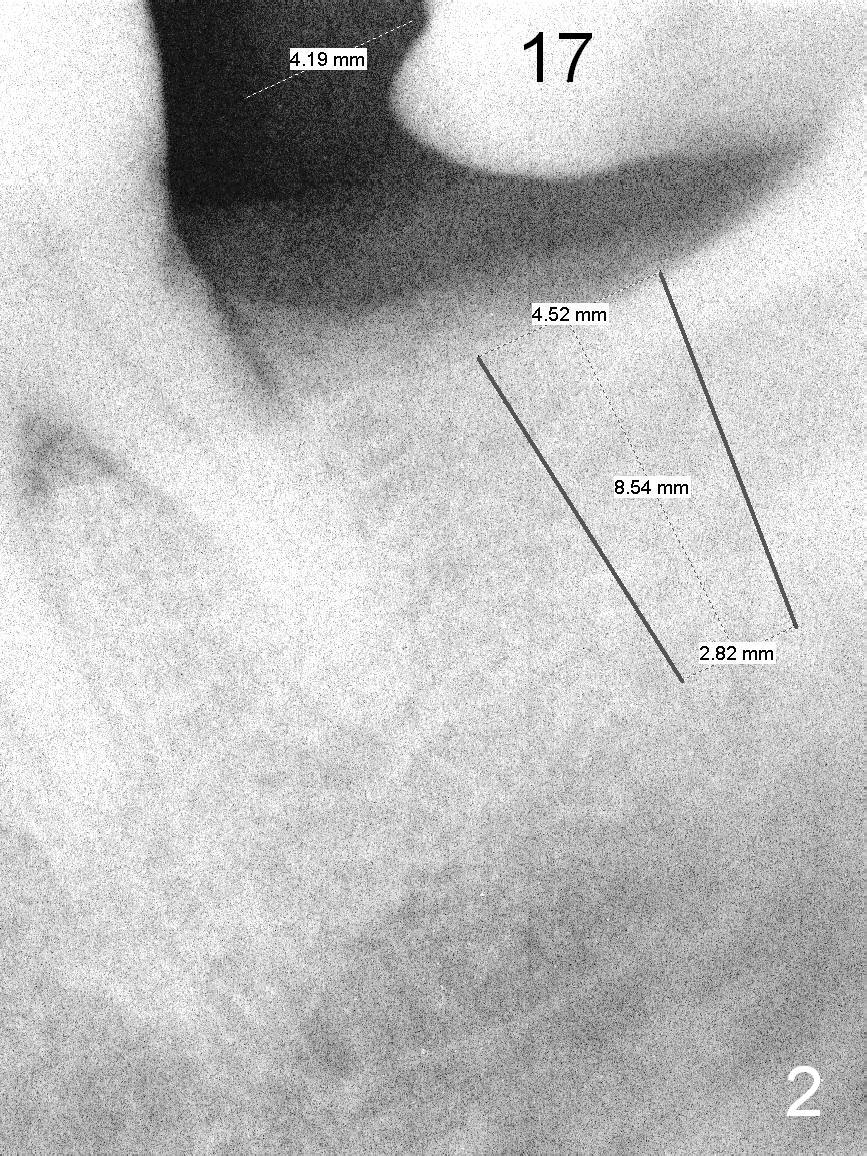

A 53-year-old lady has a small statue. The tooth #18 was extracted due to #17 impaction (Fig.1). To prevent further supraeruption of #15, an implant is to be placed at the site of #18 (Fig.2). After use of a 4 mm implant spacer and starter and 8 mm pilot drills, insert a short parallel pin for occlusion check and a calibrated one for X-ray. A relatively small and short implant will be sufficient for function. Scaling & root planing and #17 extraction have been finished.